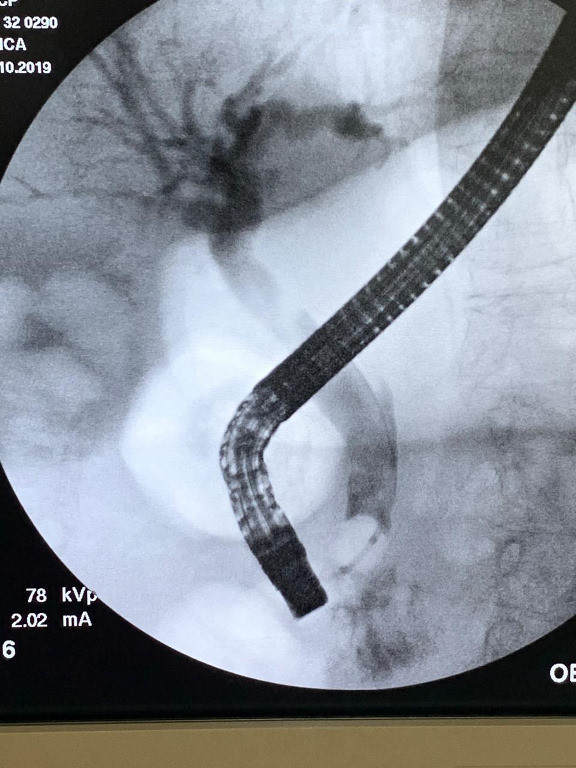

Cálculo gigante por coledocoliatisis

Post Image